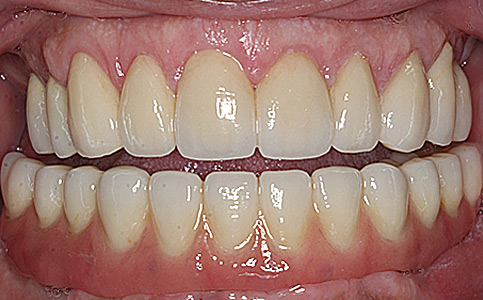

Dzięki koronom pełnoceramicznym w szczęce i żuchwie oraz uzupełnieniu braków zębowych implantami, pacjentka może znów się szeroko i pięknie uśmiechać.